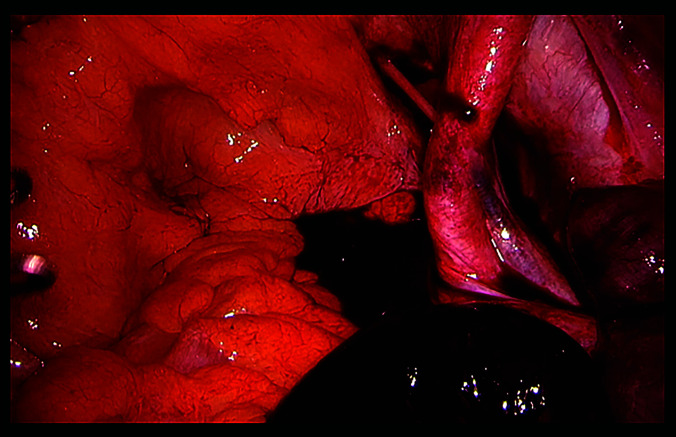

Presentation of the case: We report a case of 74-year-old male patient who presented with diffuse abdominal pain. He had undergone robot-assisted laparoscopic prostatectomy 4 months earlier. Computed tomography showed signs of internal herniation under the right external iliac vessels. The patient was operated laparoscopically with small bowel resection and peritoneal flap.